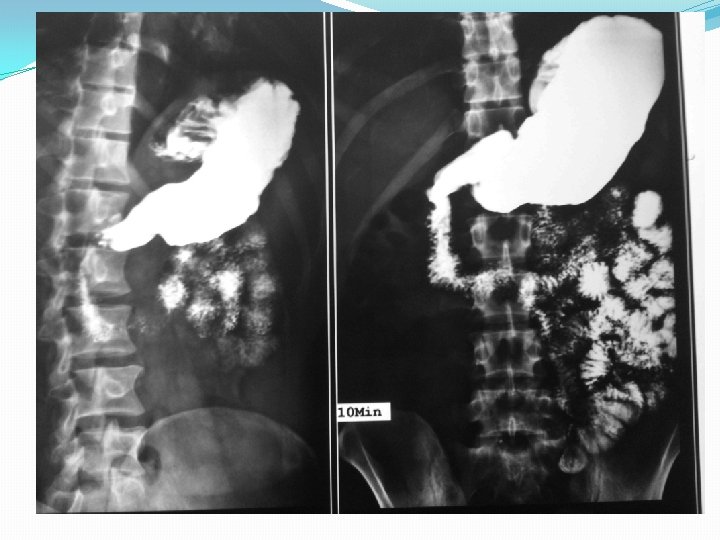

Barium studies of the gastrointestinal tract may suggest the diagnosis but are neither sensitive nor specific. They typically reveal thickening or nodularity in the antrum and a thickened or "sawtooth" mucosa in the small bowel.